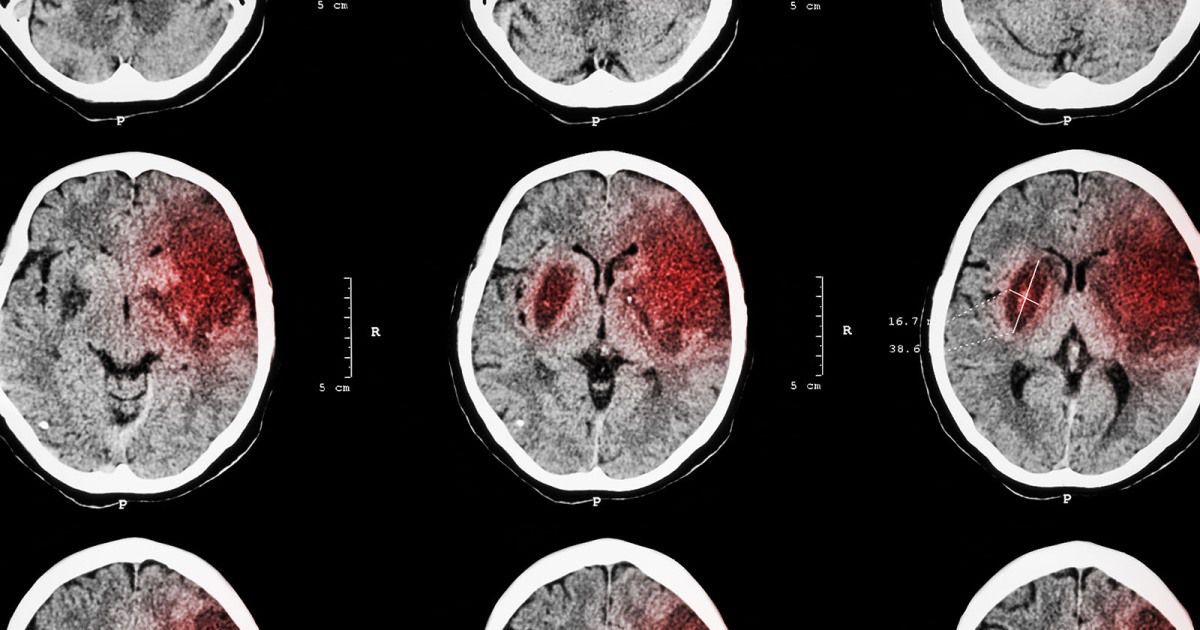

An already-approved drug could help repair the brain after a stroke

Gabapentin, which is currently used to control seizures and manage nerve pain, might help nerve cells regrow in the brain.